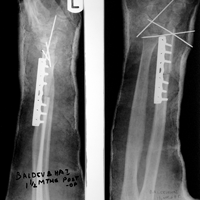

Case:5 Ewing sarcoma with implant failure

Breakage of Nail

Refixation with Angle Bladed Plate and Sever Graft

Ewing's Post Nailing and Bone Grafting

3 Months Post -Op

6 Months Post-Op